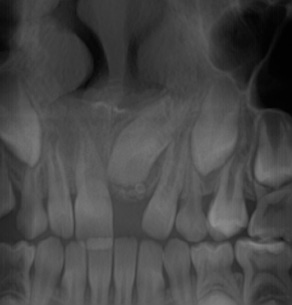

Recently, there has been improvement in X-ray diagnostic imaging methods, especially with regard to CBCT, which certainly facilitates arriving at diagnosis as early as at the stage of radiological examination. Jayam et al. describe a case of an 11-year-old girl with a radiological picture (panoramic radiography, a tooth X-ray and a maxillary occlusal radiograph) description of impacted tooth 11 with an additional cusp and an extensive dentigerous cyst.2 In the course of marsupialization, the dentigerous cyst was found to have no contact with tooth 11, while it contacted the adjacent additional cusp. On histopathological examination, OCp was diagnosed with a cyst. According to some authors, X-ray images – panoramic radiographs and targeted dental X-rays – may not accurately reveal the pattern of the lesion, which is why cross-sectional CBCT is recommended in the case of doubts or for more accurately determining the location.2 In the case of 2 of our patients, it was not until a CBCT was performed that the adequate diagnosis was reached, and it was later confirmed during the procedure and histopathological examination. The first patient was a 9-year-old girl referred to an orthodontist in our clinic due to impacted tooth 21 for the exposure of the tooth and the application of a bracket to the crown of tooth 21. The patient had with her a current panoramic radiograph with visible impacted tooth 21, showing a small non-distinctive radiopacity in the tooth crown, which could be consistent with an additional cusp. An X-ray of tooth 21 was performed at our clinic, revealing a non-distinctive area of radiopacity next to the crown of tooth 21 (Figure 7). The patient was referred for cross-sectional CBCT. After verification, OCp was diagnosed and removed with its capsule, and an orthodontic bracket was attached to tooth 21 in local anesthesia (Figure 8). Histopathological examination confirmed the preliminary diagnosis of OCp. The other patient was a 5-year-old girl who was admitted to our clinic with a missing deciduous tooth 65. The patient had a current panoramic radiograph with her, revealing an impacted tooth (most probably tooth 65) with a non-distinctive area of radiopacity (Figure 9). Cross-sectional CBCT was recommended. In the X-ray image, the preliminary diagnosis suggested OCp with the impacted deciduous tooth 65 above it and the tooth bud of permanent tooth 25 on the palatal side (Figure 10). The procedure involved the resection of the impacted deciduous tooth 65 and the enucleation of the odontoma with its capsule; the tooth bud of tooth 25 was left. Due to the child’s age and her poor cooperation, the procedure was carried out in general anesthesia. Histopathological findings revealed OCp.

A total of 20 patients (13 (65%) boys and 7 (35%) girls), aged between 2.8 and 17.6 years (mean age: 8.96 ±4.20 years), were included in the study. The study involved general and local history-taking concerning chronic comorbidities and the medications received, dental history (the reason for the visit, presenting complaints), and extraoral (facial symmetry and lymph nodes) and intraoral (the number and type of erupted teeth, the assessment of the shape and consistency of the alveolar process) clinical examination. All patients underwent radiological and histopathological examination. Depending on the indications, tooth X-rays, panoramic radiography, CBCT and/or CT were performed. Radiological imaging was used to assess the location and type of odontoma, the presence of impacted or retained teeth, gaps, and tooth displacement. While OCp were found in X-ray images as high-density radiopacities arranged as numerous small deformed denticles (odontoids) surrounded by a band of radiolucency with an osteosclerotic border, OC were characterized by irregular radiopacities with a radiolucent edge and an osteosclerotic rim. The treatment of choice for all patients was the enucleation of the tumor with the capsule surrounding it.

Radiographically, OC is a highly dense radiopacity of irregular shape, surrounded by a band of radiolucency with a sclerotic rim,6, 19 and OCp is a dense radiopacity arranged as numerous small deformed denticles (odontoids) surrounded by a band of radiolucency and a sclerotic rim.6 Similar radiological pictures were obtained for our patients. Histopathological examination should be conducted to confirm the clinical and radiological diagnosis. On microscopic examination, OCp is described as fragments of the dental pulp, dentin, enamel matrix, epithelium, and connective tissue, or as fragments of a tooth with preserved histological structure, with fragments of fibrovascular tissue. On the other hand, OC is described in histopathological findings as fragments of dentin and connective bone tissue. The histopathological picture of OC is very similar to that of an ameloblastic fibro-odontoma (AFO).20, 21 And this was the microscopic picture obtained for the lesions removed in our patients.